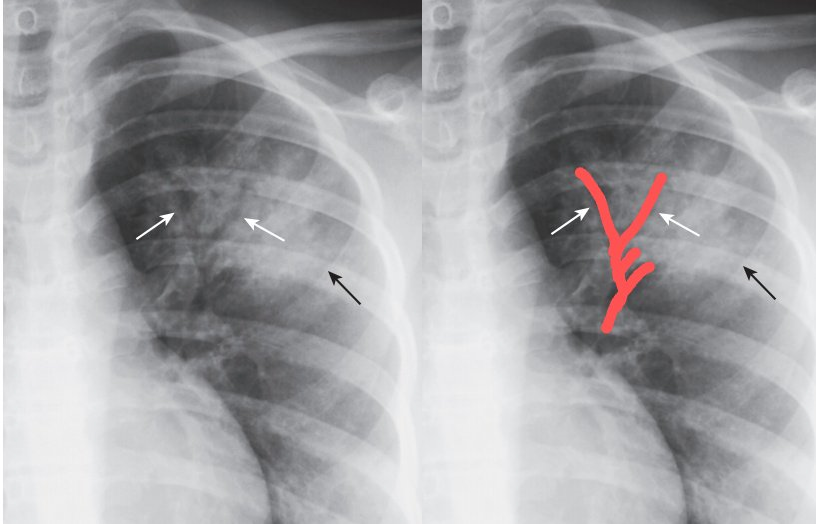

- Normalmente los bronquios no se ven porque estan rodeados de aire. El broncograma aereo se define por la visibilidad anormal del aire de los bronquios en el seno de la opacidad. Este es un signo cierto de lesión alveolar, y al mismo tiempo nos revela también que la patología se encuentra ubicada dentro del parénquima pulmonar y por último confirma que la luz del bronquio está permeable. En la neumonia la consolidacion sustituye este aire asi que los bronquios se ven como las ramas de un arbol porque tienen aire en su interior, en contraste con la opacidad que los rodea.